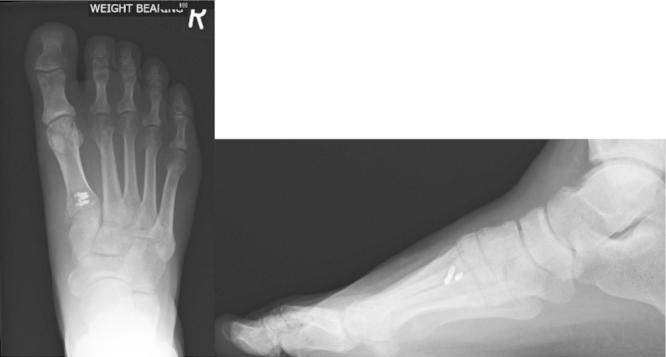

A 48 year old male sustained a crush injury to his right foot when it became stuck in a vertical industrial fan at work. He attended A & E complaining of swelling of the dorsum of foot. On examination, there was tenderness at the base of the first metatarsal. X-ray revealed an avulsion fracture of the first metatarsal, and MRI showed rupture of tibialis anterior. The patient underwent surgical repair 10 days later, with post-operative management in a non-weight bearing, then weight bearing cast. X-ray at 8 weeks showed that the fracture had healed. The patient had a course of physiotherapy and was followed up at 6 months to assess pain and function.

一名48岁男性在工作时右脚卡在垂直的工业风扇中,导致右脚挤压伤。他前往急诊室就诊,主诉足背肿胀。检查时,第一跖骨基部有压痛。X线显示第一跖骨撕脱骨折,磁共振成像(MRI)显示胫前肌腱断裂。患者10天后接受了手术修复,术后采用非负重,然后是负重石膏固定。8周时的X线显示骨折已愈合。患者接受了一个疗程的物理治疗,并在6个月时进行随访以评估疼痛和功能。